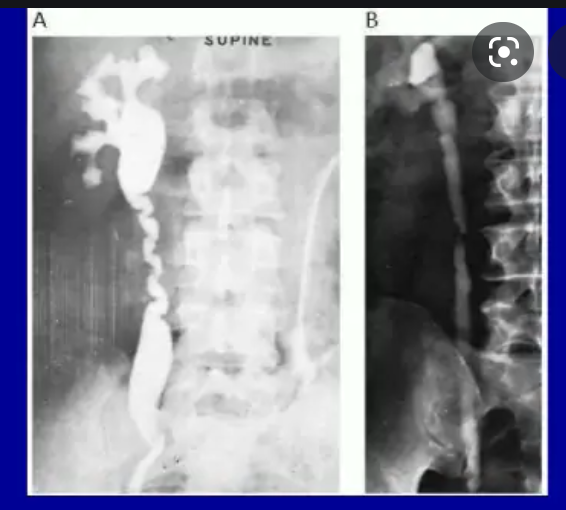

A 47-year-old male with right flank pain. (a) A magnified view from a control film of an intravenous urogram (IVU) demonstrates a 2 cm opacity in the right upper quadrant (arrow). This image clearly shows that the opacity is made up of multiple tiny calculi rather than a single large calculus, which should raise the suspicion that they lie within a calyceal diverticulum. (b) An oblique radiograph from a retrograde pyelogram study elegantly depicts the short, narrow infundibulum of a calyceal diverticulum arising from a mid-pole calyx (arrow).

https://www.birpublications.org/doi/10.1259/bjr/22591022